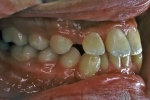

治療中